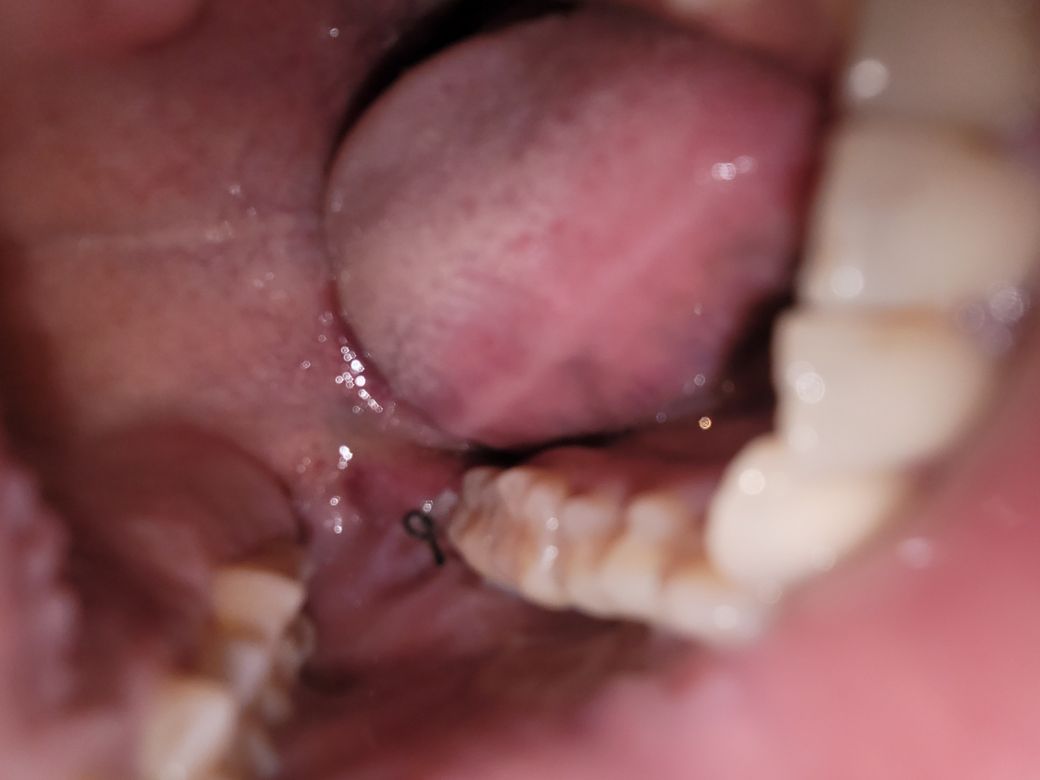

매복사랑니 발치 후 3일이 지났습니다

초점이 흐려서 잘 보이실지는 모르겠네요ㅠ

화요일 오전에 발치했구요 당일에는 통증이 꽤 있더니

수요일에는 약을 안먹어도 괜찮을 정도로 통증이 없었습니다

그러고 자고 일어나니까 다시 통증이 심해지고 붓기도 올라와서 씹기도 불편하더라구요 참을만한 통증이기는 하지만

다른 이상은 없을지 궁금합니다

• 1번 째 사진

사진상으로 붓기가 아직 있는것으로 보입니다.

매복치 발치의 경우 잇몸절개, 골삭제 등이 동반되기 때문에, 술후 심한 통증, 붓기가 생길 수 있습니다.

붓기는 3일째되는날이 보통 가장 많이붓고, 그 이후로 보통 조금씩 나아지게 됩니다.